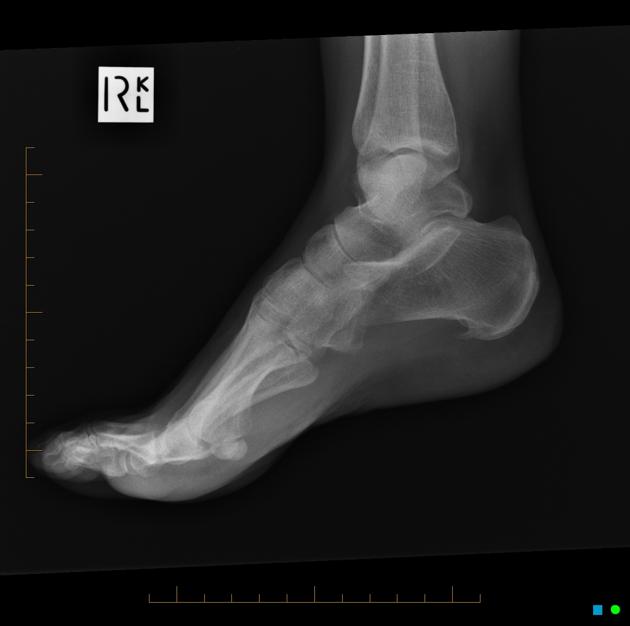

근위부의 경우 족저근막 이라는 인대가 붙어 있는 부위 위기 때문에 날카롭게 뼈모양이 변하는 골극이 발견되는 경우 족저근막염이 쉽게 발견될 수 있습니다.

실제로 아래와 같이 X-ray 나 MRI 에서 쉽게 발견할 수 있습니다. (잘 안보이는 경우 내측으로 45도 비스듬하게 찍기도합니다.) 골극은 주로 FDB의 기시부에 위치합니다. 본 스캔 검사를 통해서(핵의학검사) 족저근막염을 확인해 볼 수도 있습니다.